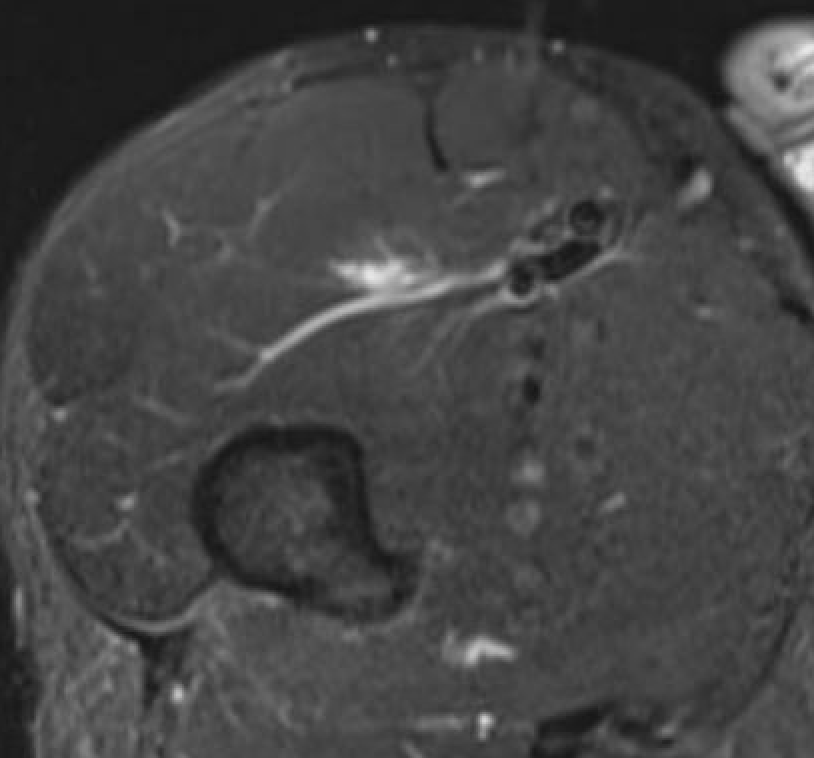

Grade 2B proximal rectus femoris muscle

Grade 3B proximal rectus femoris muscle